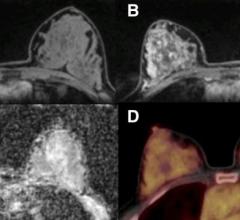

Despite decades of progress in breast imaging, one challenge continues to test even the most skilled radiologists ...